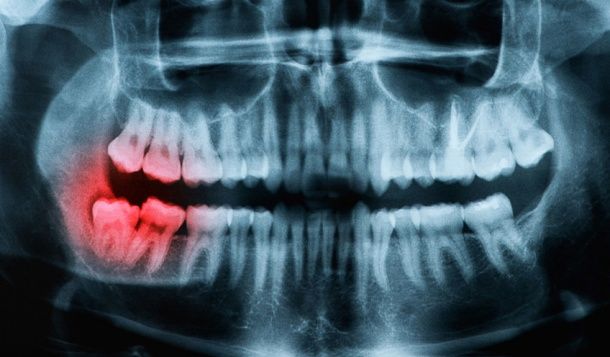

Extracción de las muelas del juicio

Frecuentemente las muelas del juicio no pueden salir espontáneamente y quedan impactadas dentro del hueso mandibular provocando problemas de dolor, infección e incluso perjudicando a las muelas vecinas. El tratamiento es exclusivamente la extracción de dichas muelas del juicio.

¿Deben extraerse siempre las muelas del juicio?

• No si no nos dan problemas. Las razones para extraer una muela del juicio son bien por patología de la propia muela como caries grandes con infecciones, pericoronaritis que son las inflamaciones e infecciones en el proceso de erupción de la muela que no tiene espacio para salir y por último en casos de ortodoncia cuando la presión que ejercen al erupcionar tiene riesgo de mover otras piezas.